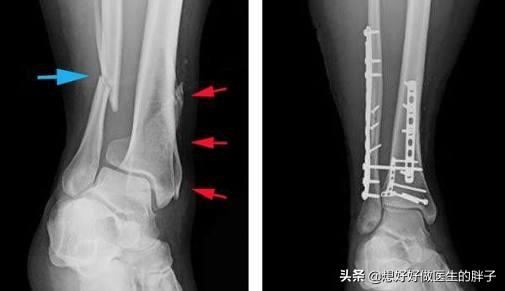

小腿有两根重要的骨头,一根是胫骨,一根是腓骨,小腿骨折根据骨骼损伤的位置可以分为胫骨骨折、腓骨骨折或者胫腓骨双折;而不同骨折又可以分为多种骨折方式,比如闭合骨折、开放骨折、螺旋骨折、粉碎骨折等等,这又可以分为是否存在血管损伤、是否有筋膜室综合征等并发症,所以简单谈论小腿骨折以后如何快速恢复有些复杂,所以我们将小腿骨折设置为:小腿胫腓骨双折、钢板内固定术后,如何能恢复的安全、快速呢?这样会更好的帮助大家理解骨折的基本注意事项,和如何康复,何时康复更好!